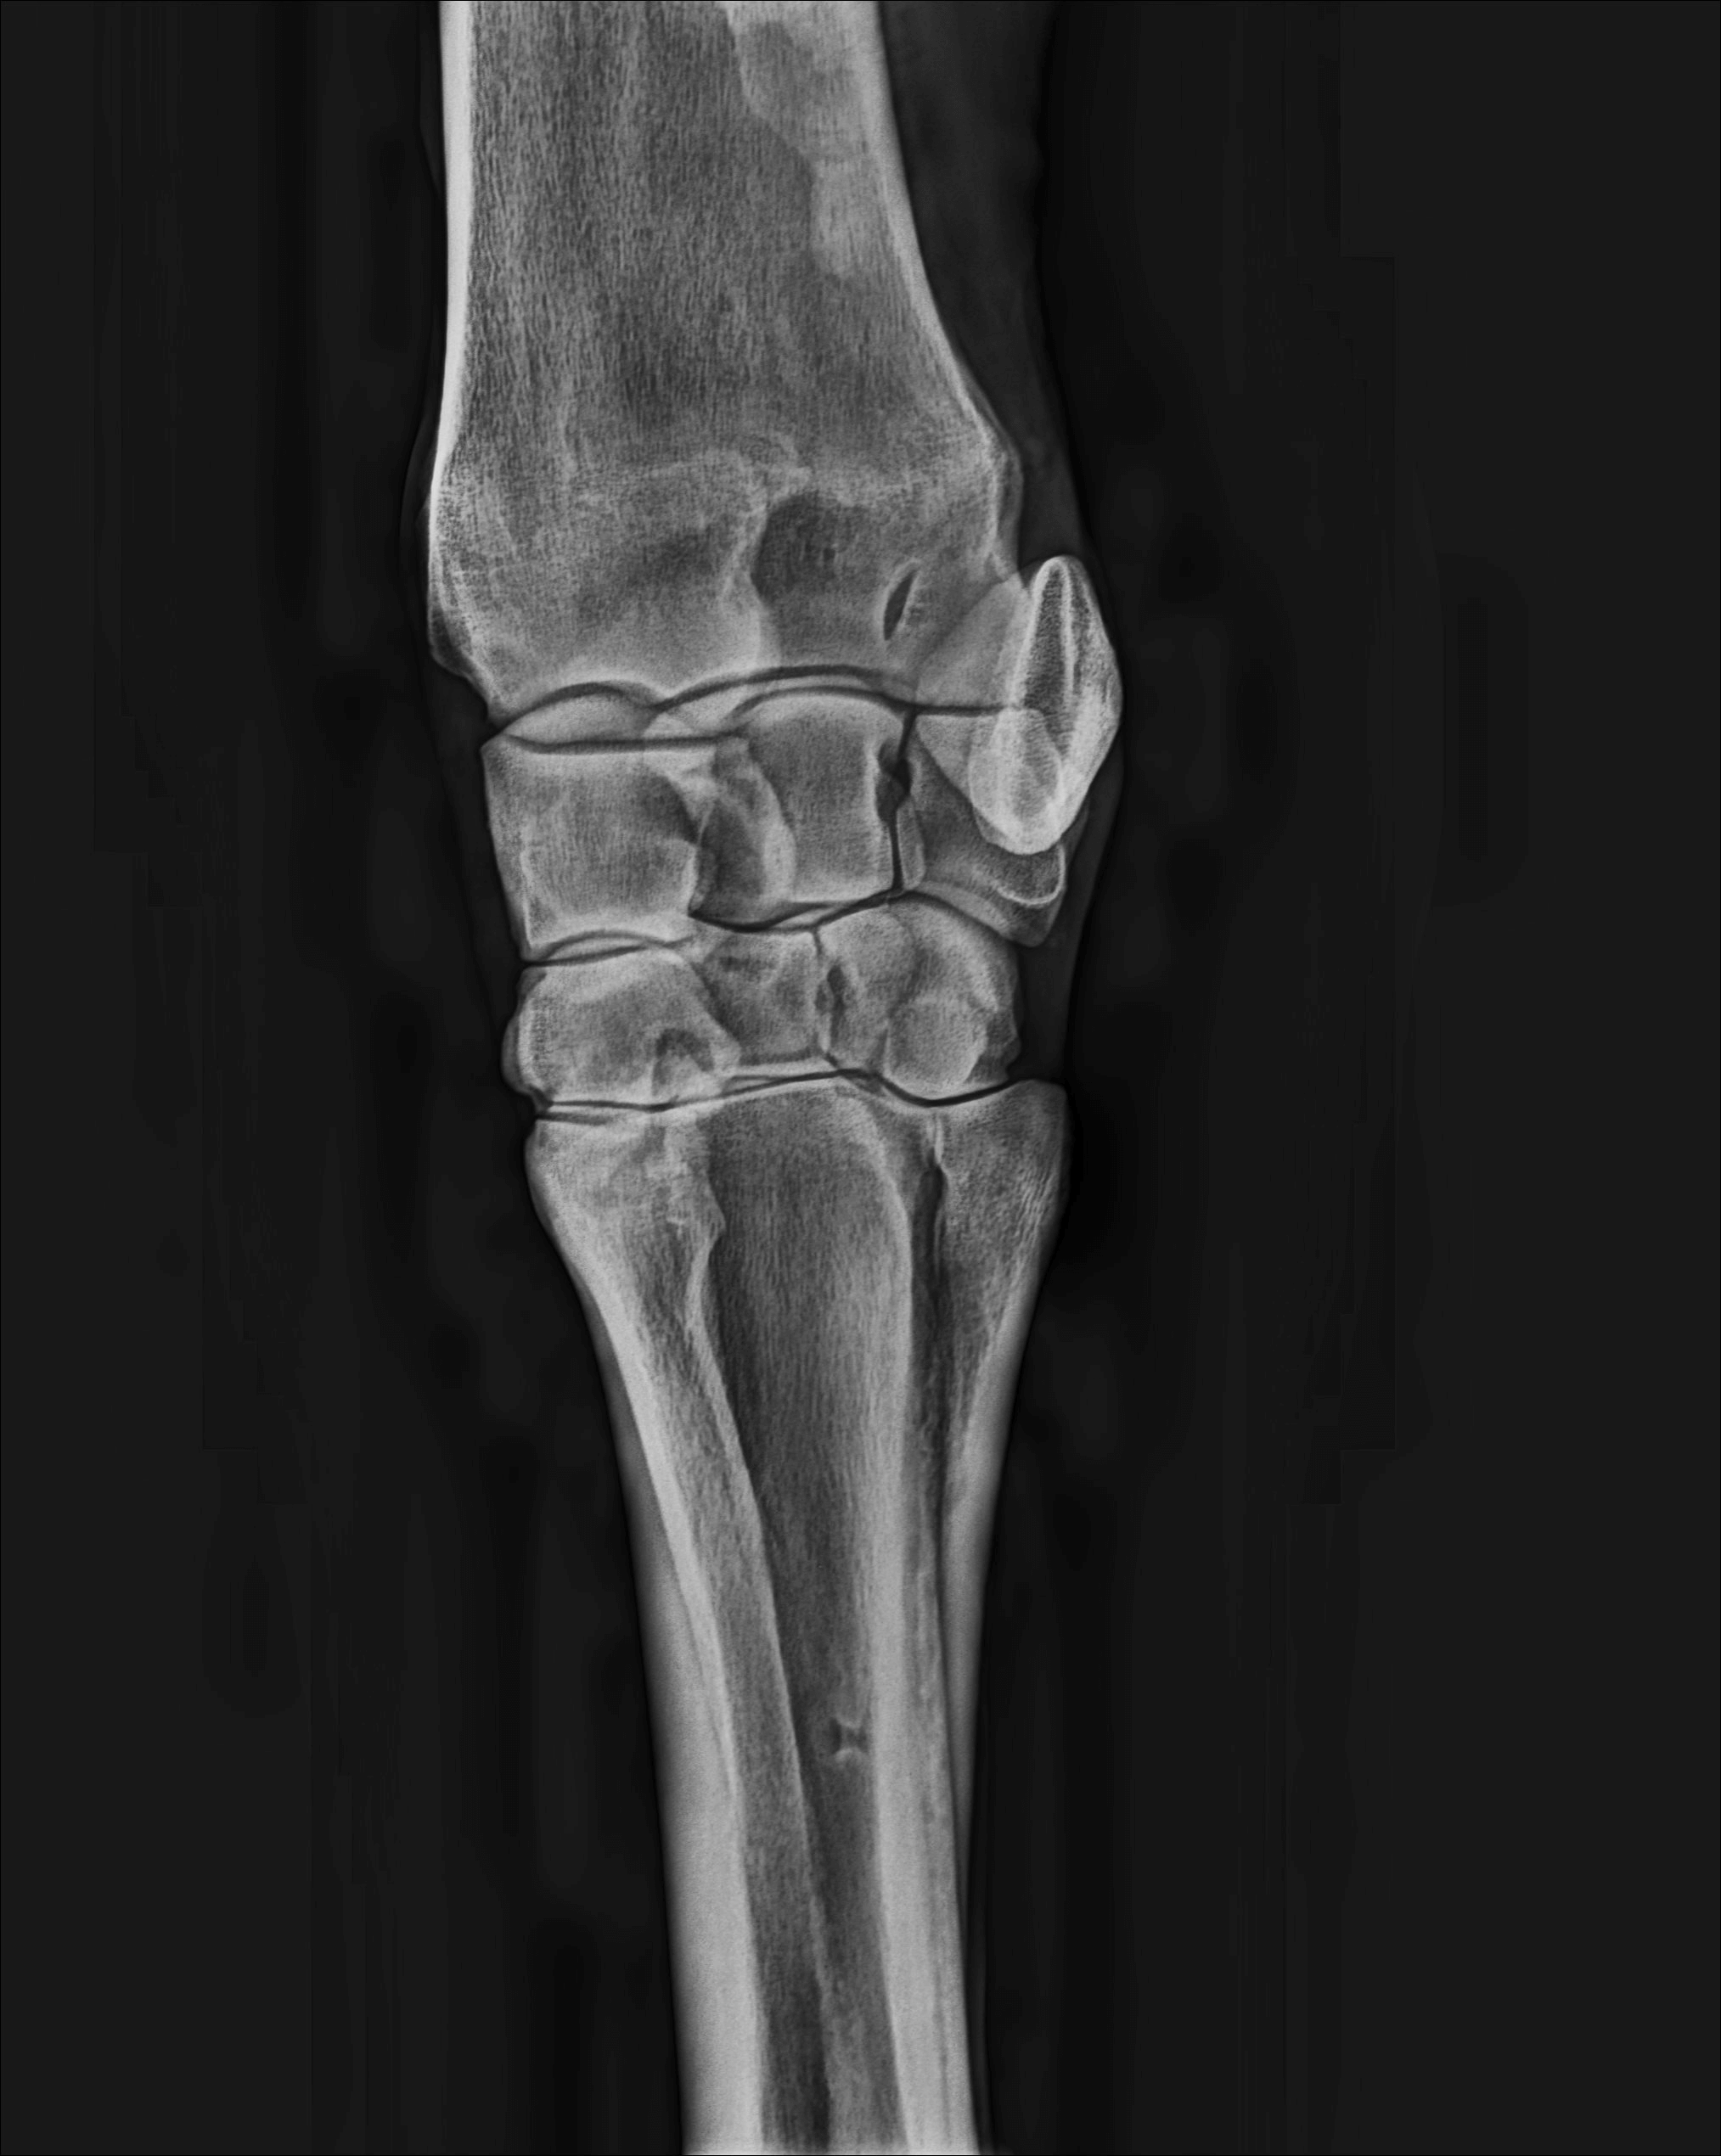

We have been blown away by the image quality with our new equipment. This improves our ability to diagnose musculoskeletal and joint issues causing lameness in horses, as well as a range of other medical conditions.

We are able to highlight different anatomical features within the one image, improving diagnosis of lameness, medical conditions and dental conditions.